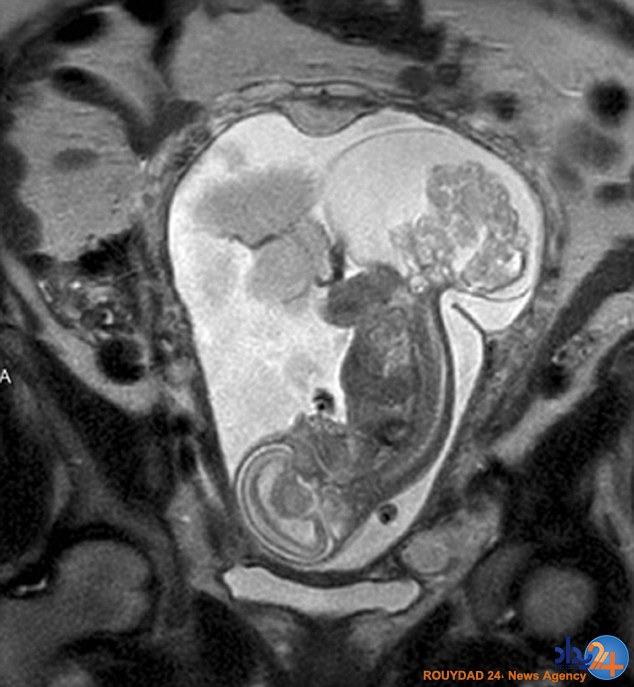

به گزارش رویداد۲۴ به نقل از دیلی میل، تولد اصلی این نوزاد 12 هفته پسازآن صورت گرفت که پزشکان او را از رحم مادرش بیرون آوردند تا با عمل جراحی جانش را نجات دهند.

پزشکان توموری را در دنبالچه این نوزاد هنوز متولد نشده شناسایی کرده بودند و برای درمان آن مجبور شدند، در 16 هفتگی او را از رحم مادرش خارج کنند.

تنها راه نجات او انجام این عمل جراحی بود که باعث شد جراحان او را به مدت 20 دقیقه به این دنیا بیاورند و بار دیگر او را به رحم مادرش بازگردانند.